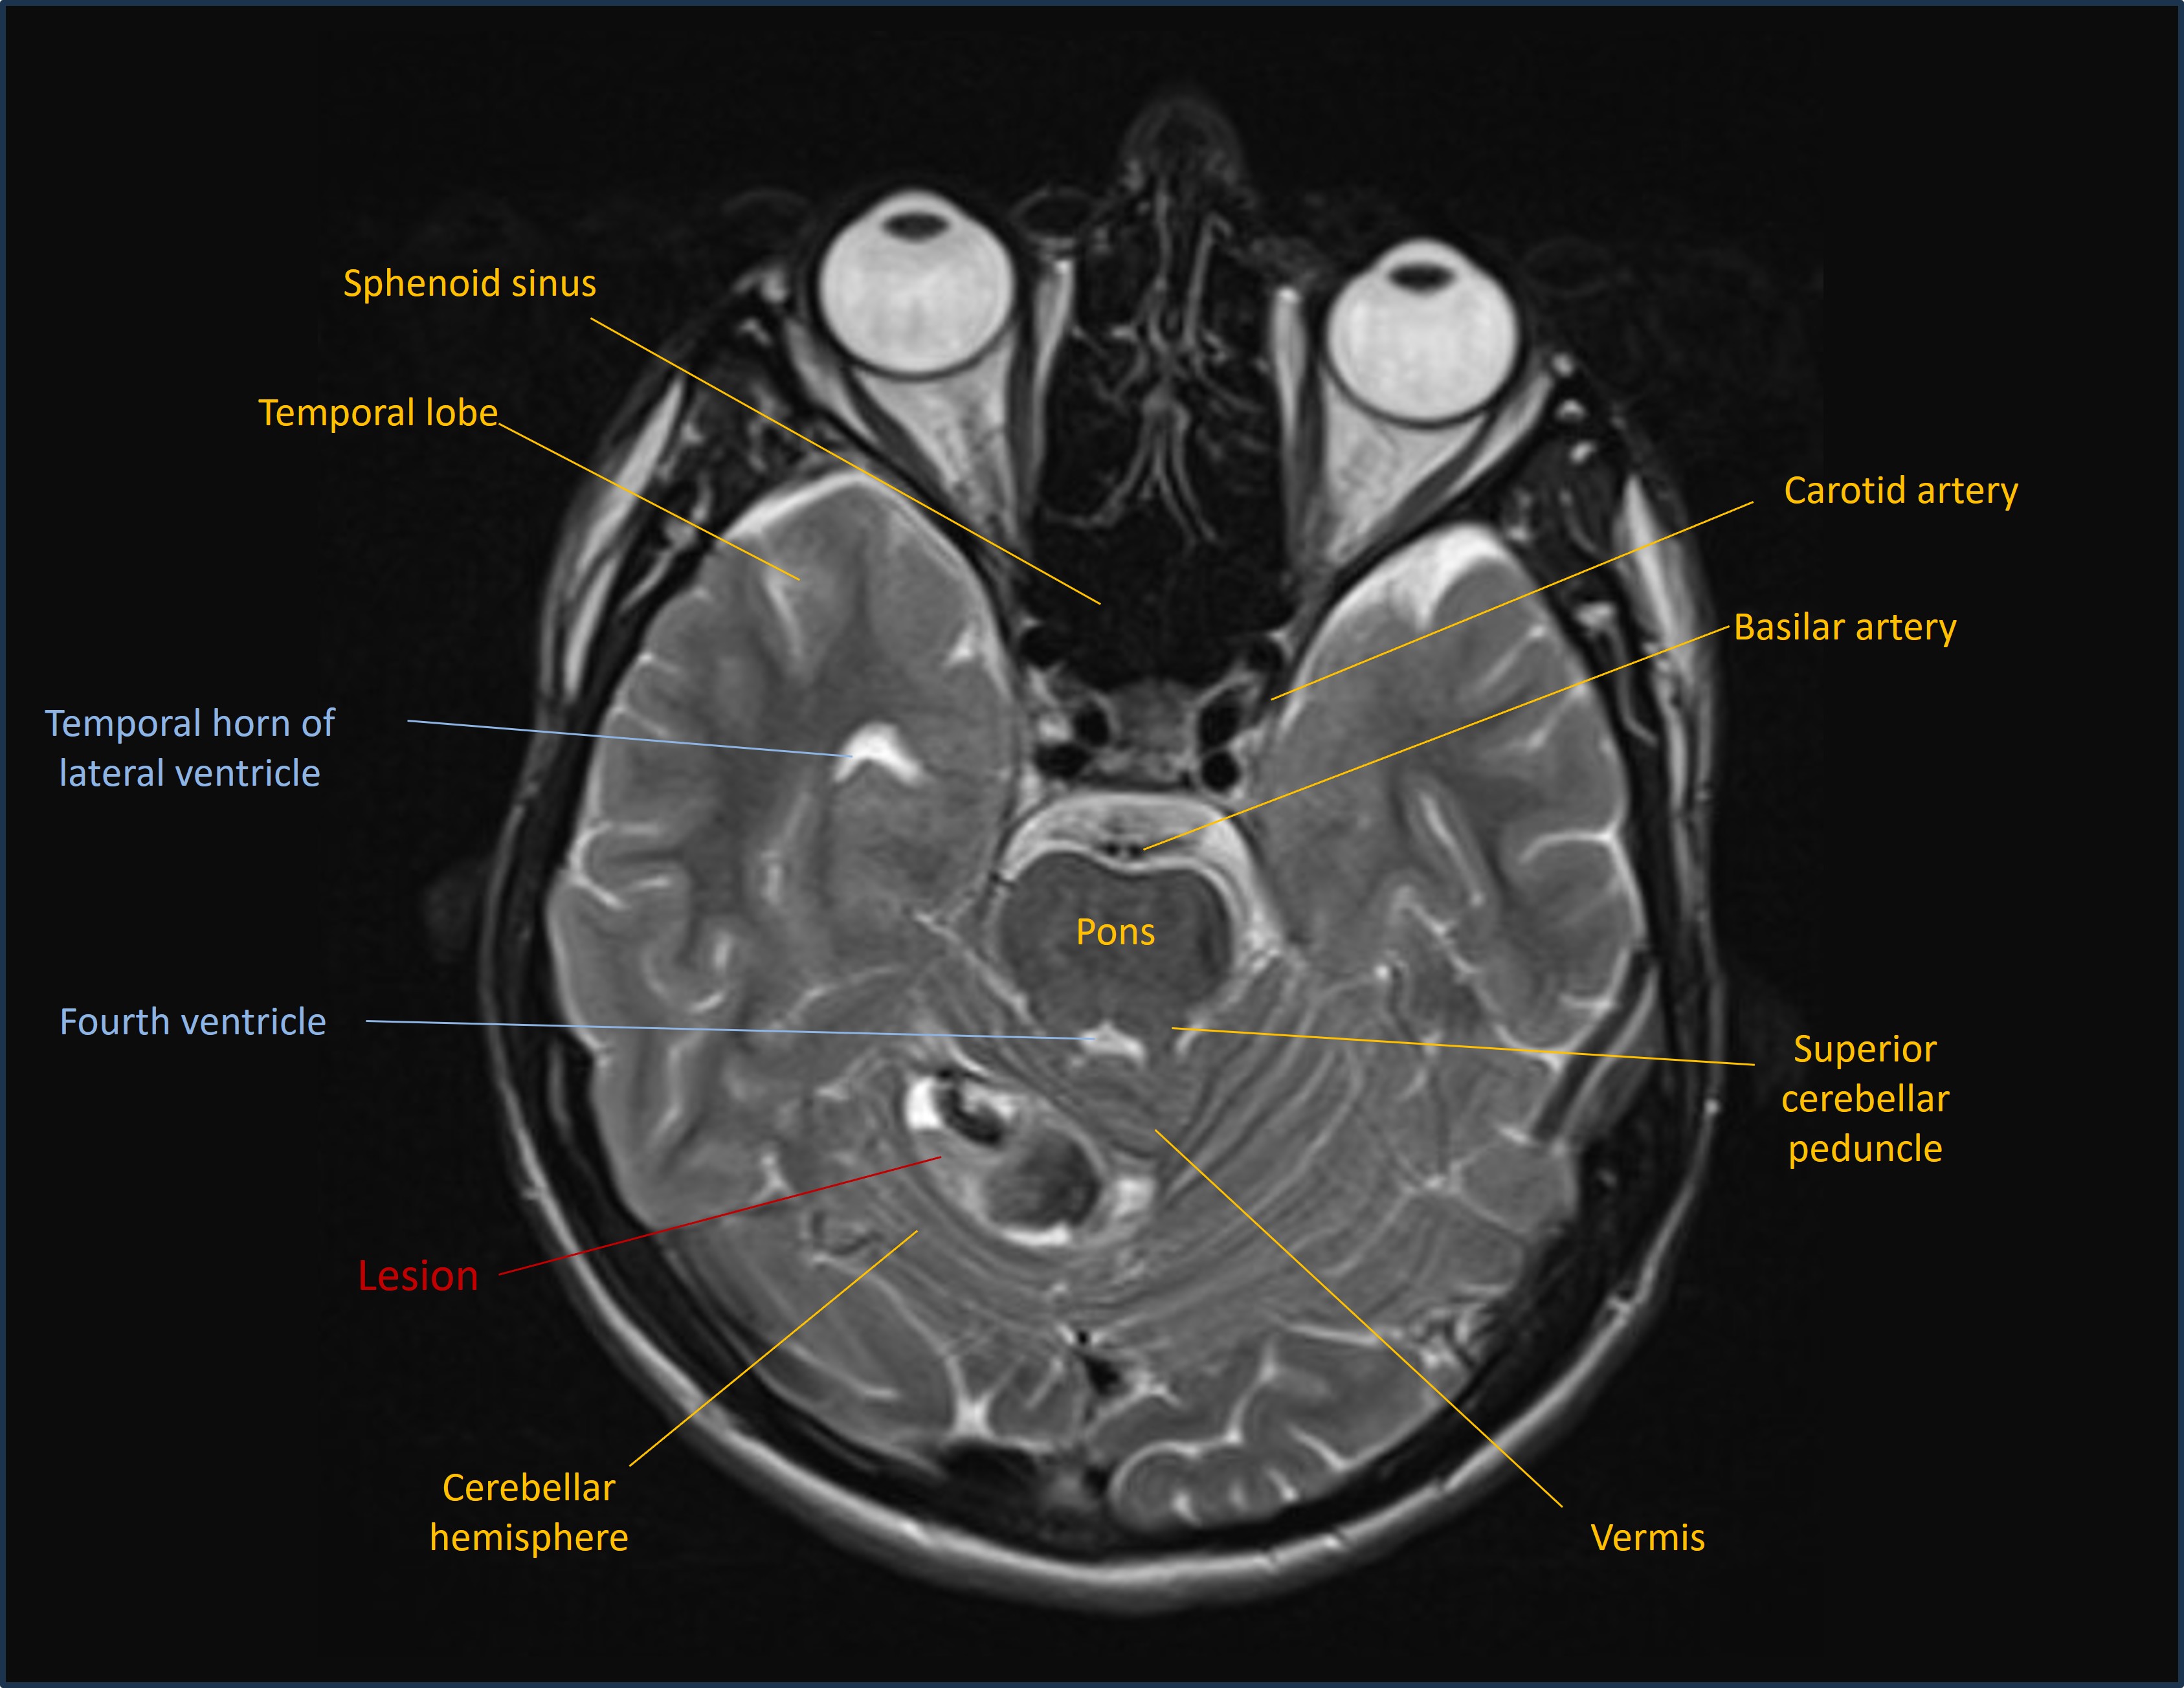

MRI showed a lesion in the right cerebellar hemisphere, with appearances suggestive of a recent haemorrhage surrounding an underlying lesion - shown on the sagittal T1 and axial T2 MRI images below: .

Axial MRI

A differential diagnosis was suggested, including tumour, but the imaging was thought most likely to reflect an underlying cavernoma.